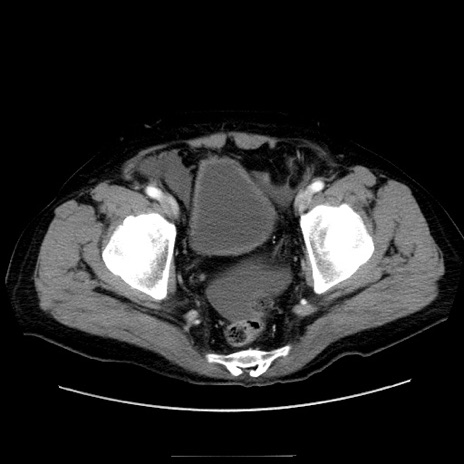

症例30(横断像)

【症例】80歳代男性

【主訴】臍周囲痛

【現病歴】約6時間前から臍下部痛が出現。次第に腹部膨隆・背部痛も生じてきたため来院。背部痛の場所は変化しない。

【既往歴】腎盂腎炎

【身体所見】意識清明、BT 36.3℃、BP  131/87mmHg、P 87bpm、SpO2 100%(RA)、臍周囲自発痛・圧痛あり、反跳痛なし、自発痛部位に一致して板状硬あり、腹部膨隆、腸雑音減弱、CVA tenderness両側陰性。

【データ】WBC 19600、CRP 0.33